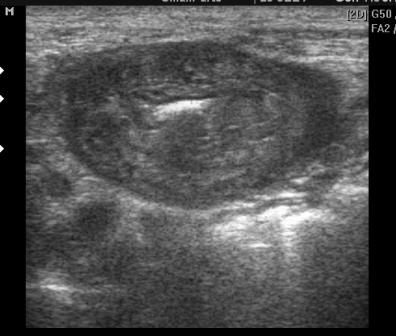

Мужчина из психоневрологического интерната с жалобами на боль в животе.

на сппо вроде не тянет, слоистость стенки сохранена

Да,слоистость сохранена , но смутила толщина стенки 8-10мм. Создалось впечатление, что с участком желудка что-то не так, а что непонятно. Возможно, просто показалось и стоит просто перекреститься))).

ФГС: атрофический гастрит. ОАК: Hb-84, СОЭ 50.

Атрофический!

Кмк стенка не утолщена. Желудок словно сокращен продольно. И если дать объем жидкости, то стенки расправятся и будут иметь обычный вид.

Cr для сравнения

Стенки кажутся сплошными, без дифференцировки на слои.